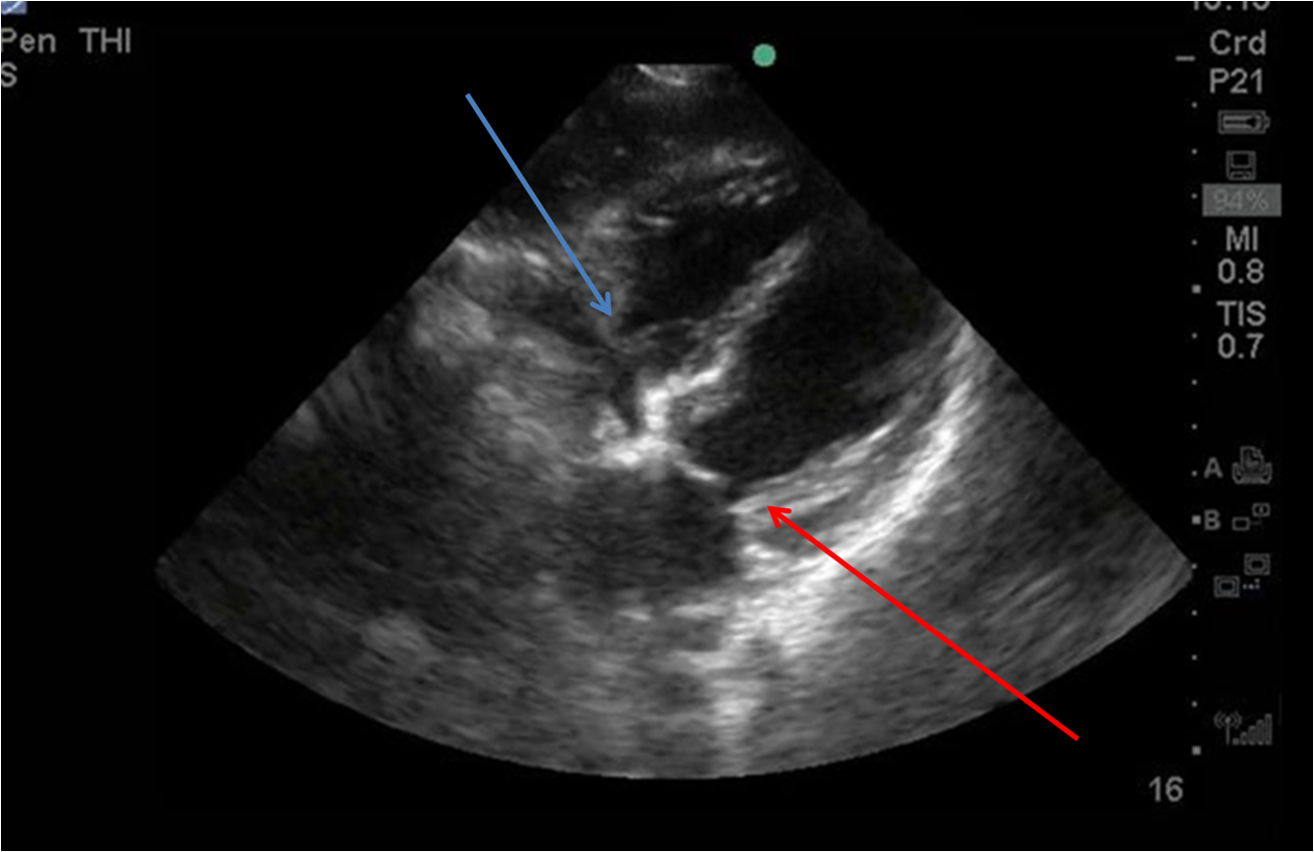

From www.emra.org

Differentiating Acute Versus Chronic Right Heart Failure with Bedside How To Do A Bedside Echo Bedside echo is becoming an integral part of intensive care medicine, offering real time haemodynamic evaluation. Bedside ultrasound should be used to answer specific questions in real time. How to do a level 1+ echo. Ultrasonography is frequently used in the ed in diagnostic and therapeutic procedures and in evaluation of critically ill patients. An example is the increasingly common. How To Do A Bedside Echo.